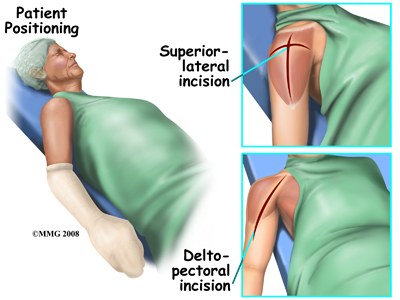

Shoulder replacement surgery is done through an incision on the front of your shoulder. This is called an anterior (deltopectoral) approach. For reverse shoulder replacements, especially for patients with multiple previous surgeries, a superior approach through the deltoid muscle may be used. No matter which approach is used, the surgeon cuts through the skin and then isolates the nerves and blood vessels and moves them to the side. The muscles are also moved to the side. If the deltoid requires cutting, a delay in your rehabilitation will be needed to allow the deltoid muscle to heal before putting stress through it.

Shoulder replacement surgery is done through an incision on the front of your shoulder. This is called an anterior (deltopectoral) approach. For reverse shoulder replacements, especially for patients with multiple previous surgeries, a superior approach through the deltoid muscle may be used. No matter which approach is used, the surgeon cuts through the skin and then isolates the nerves and blood vessels and moves them to the side. The muscles are also moved to the side. If the deltoid requires cutting, a delay in your rehabilitation will be needed to allow the deltoid muscle to heal before putting stress through it.

The reverse shoulder prosthesis (artificial joint) is made up of two parts. The humeral component replaces the humeral head, or the ball of the joint. The glenoid component replaces the socket of the shoulder, which is actually part of the scapula. Shoulder replacement surgery is done through an incision on the front of your shoulder. This is called an anterior (deltopectoral) approach. For reverse shoulder replacements, especially for patients with multiple previous surgeries, a superior approach through the deltoid muscle may be used. No matter which approach is used, the surgeon cuts through the skin and then isolates the nerves and blood vessels and moves them to the side. The muscles are also moved to the side. If the deltoid requires cutting, a delay in your rehabilitation will be needed to allow the deltoid muscle to heal before putting stress through it.

Shoulder replacement surgery is done through an incision on the front of your shoulder. This is called an anterior (deltopectoral) approach. For reverse shoulder replacements, especially for patients with multiple previous surgeries, a superior approach through the deltoid muscle may be used. No matter which approach is used, the surgeon cuts through the skin and then isolates the nerves and blood vessels and moves them to the side. The muscles are also moved to the side. If the deltoid requires cutting, a delay in your rehabilitation will be needed to allow the deltoid muscle to heal before putting stress through it.